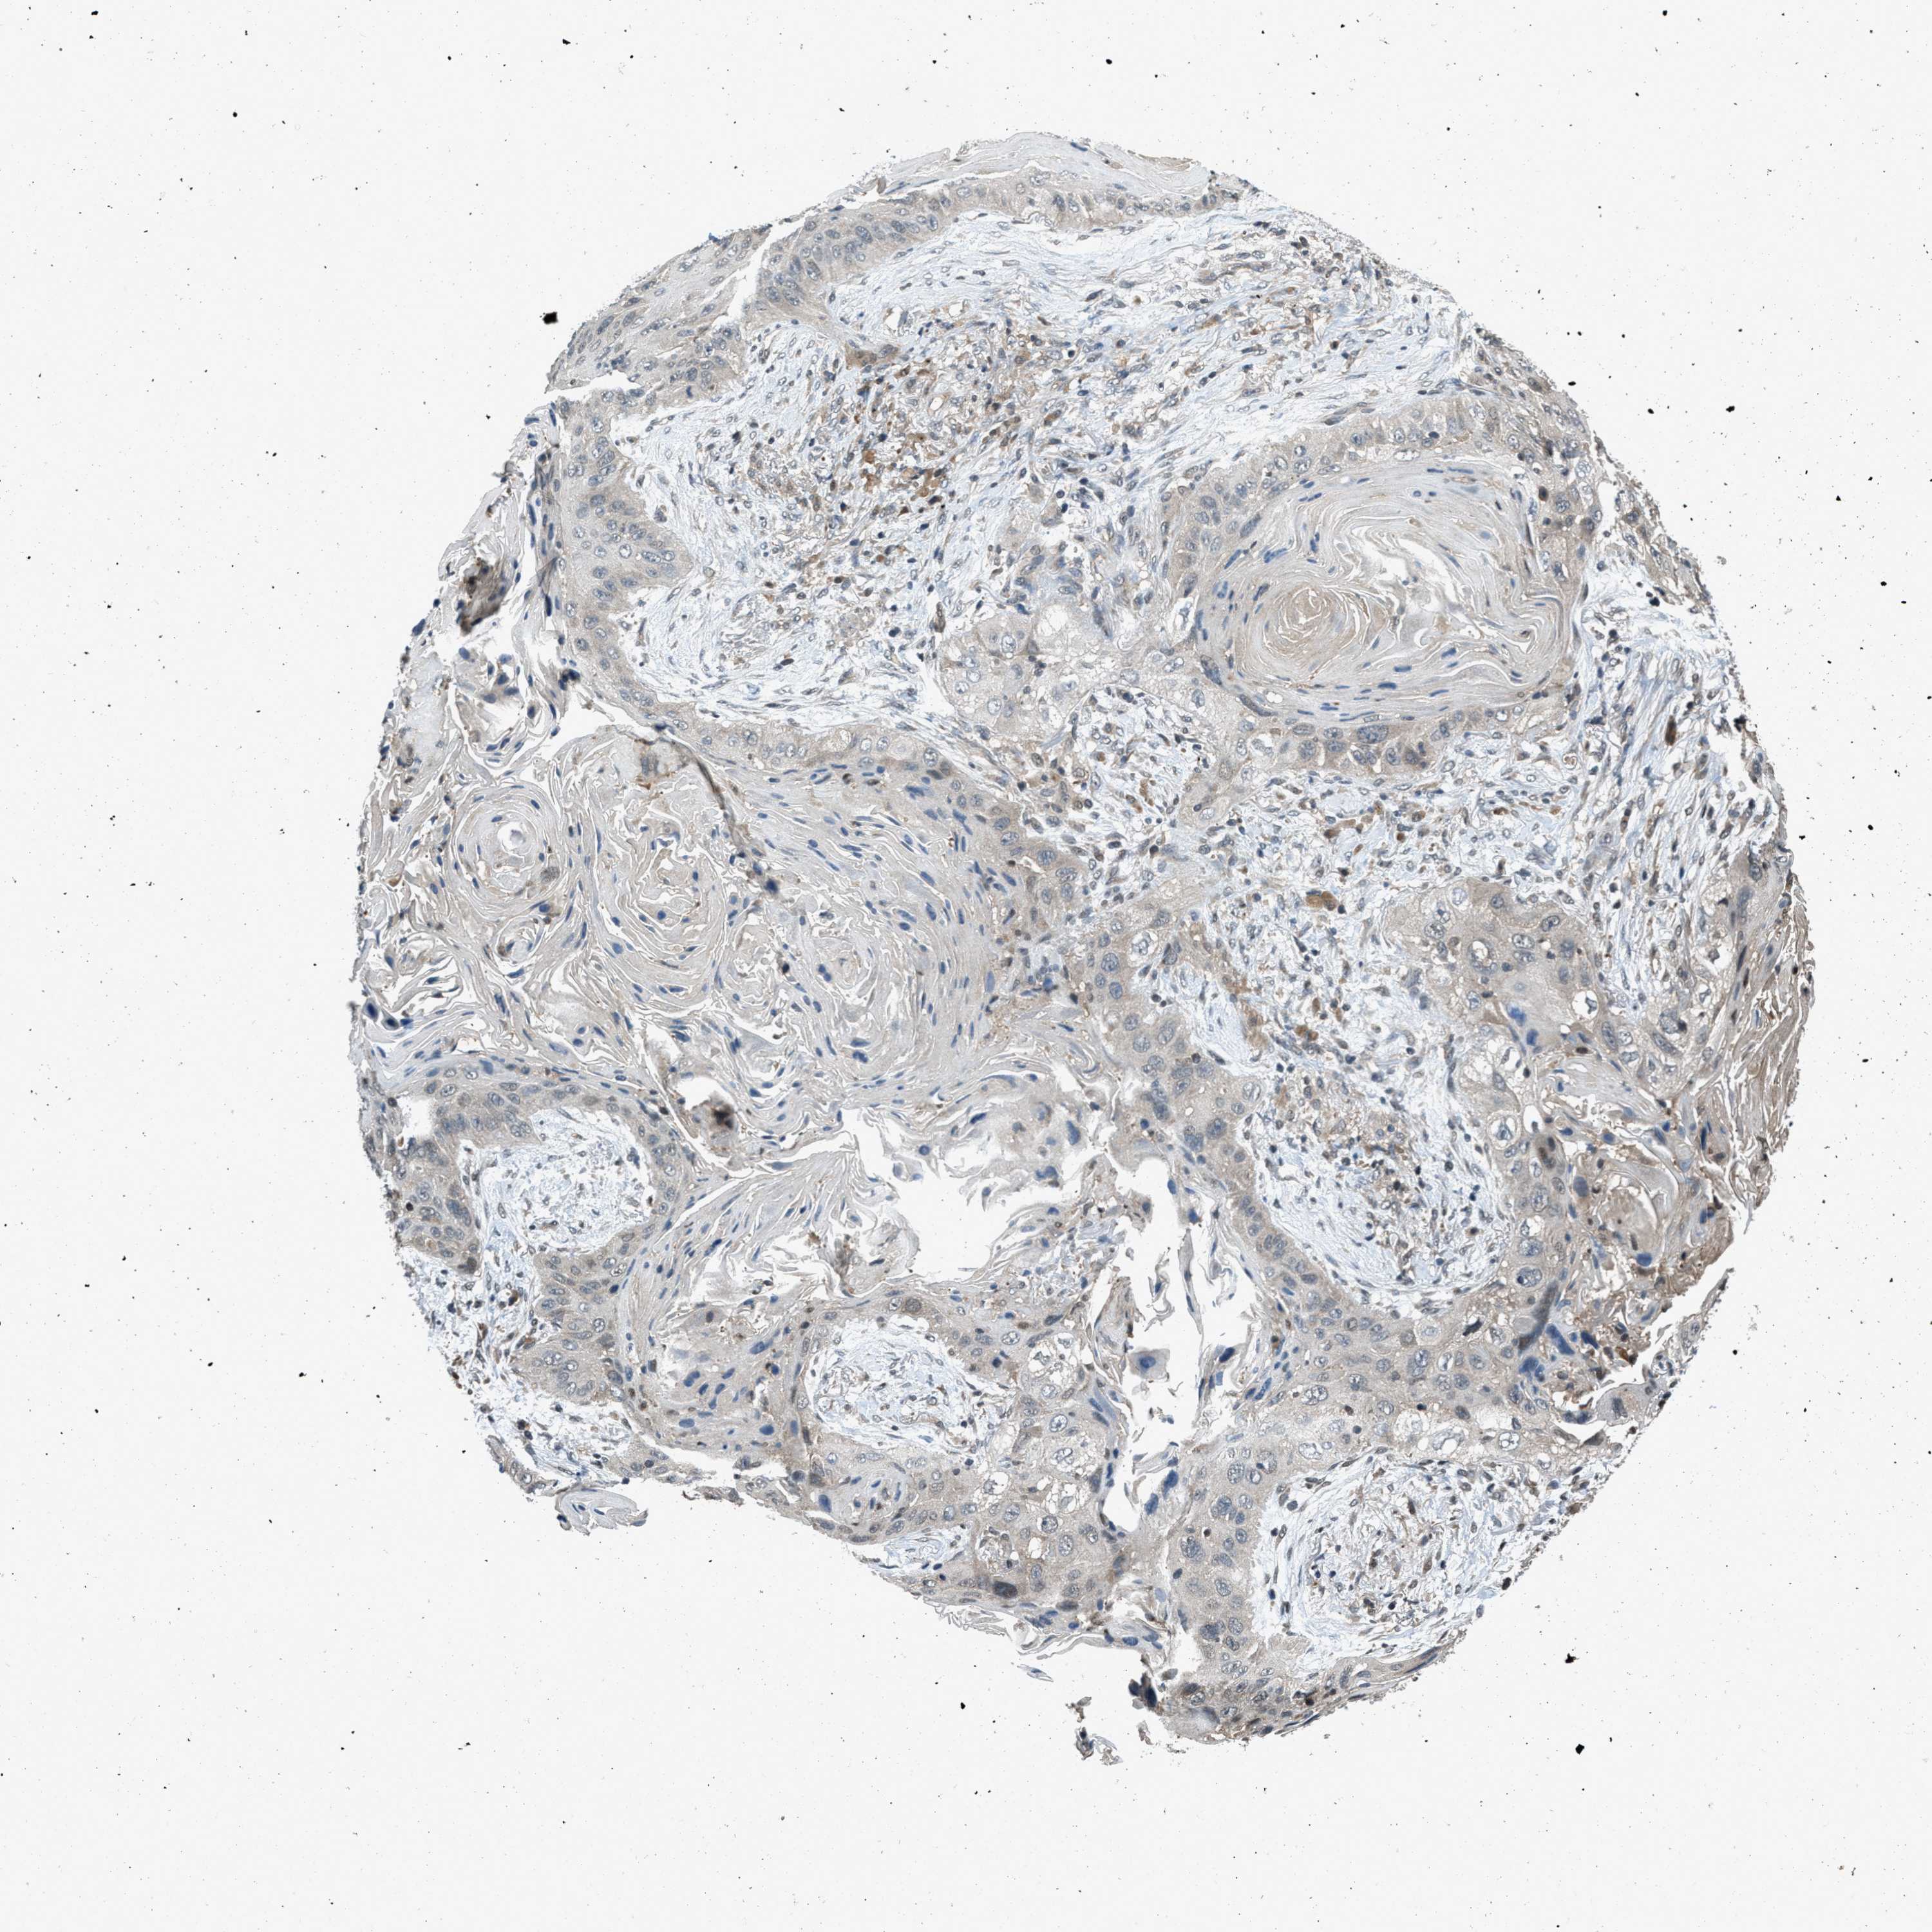

CANCER LUNG CANCER Show tissue menu